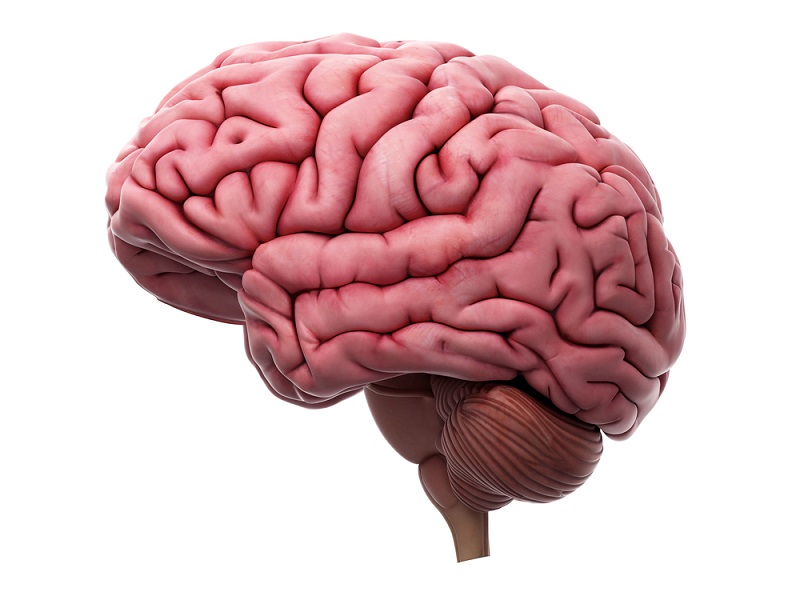

Todas las actividades voluntarias involucran al cerebro, el cual envía impulsos motores que generan el movimiento.

El córtex cerebral procesa la información sensorial y envía estos impulsos hacia los músculos. El ganglio basal juega un papel secundario en este proceso; estas masas de materia gris ayudan a controlar los movimientos coordinados, como el caminar.

El cerebelo monitorea la información sensorial de la posición del cuerpo, dando los toques finales a los impulsos motores de los nervios desde el córtex cerebral para poder coordinar el movimiento.